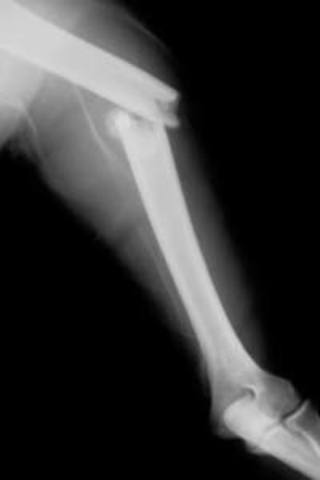

• Broken Bone

Broken Bone

my arm Was broken because, A heavy metal Thing fell on my arm.